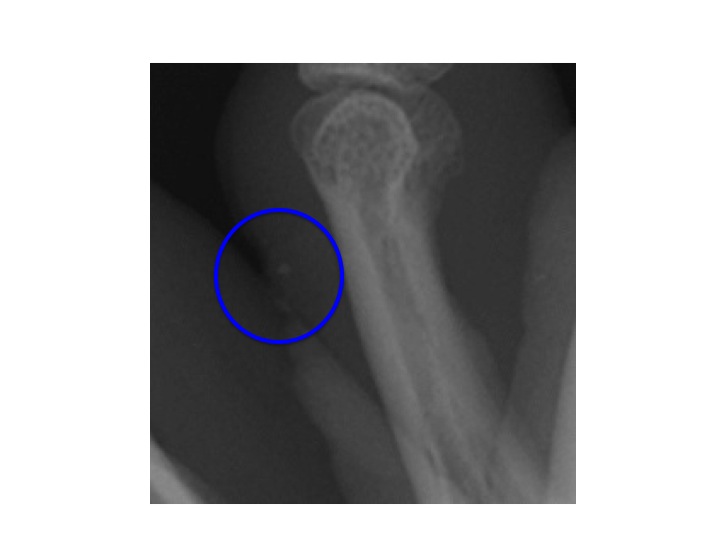

This patient has 2 pieces of glass in her elbow after an MVC. The wound has been marked with a BB to help the clinician guide removal.